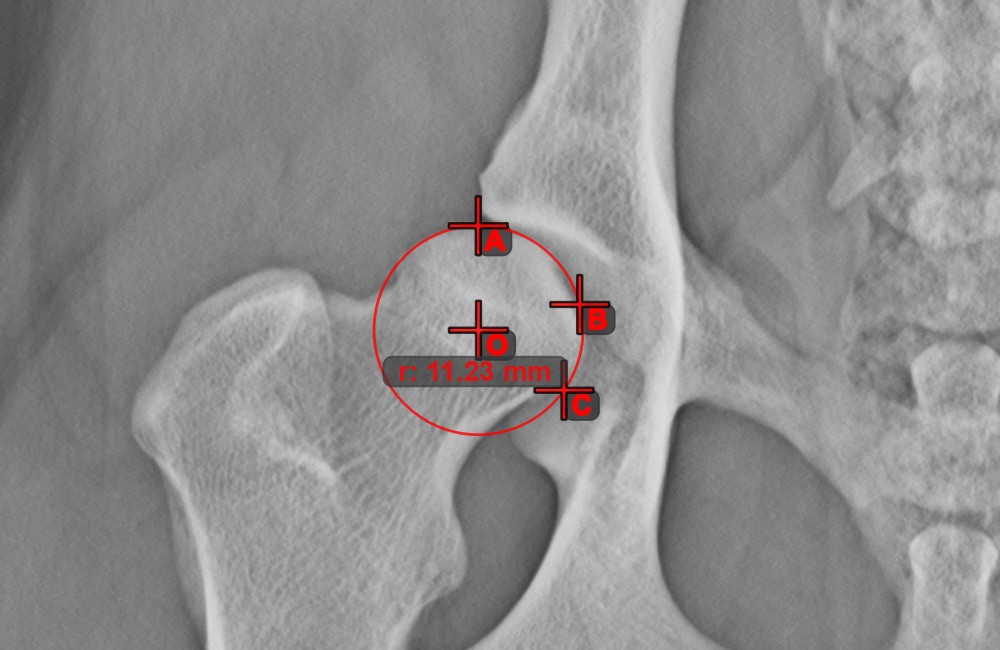

Kreis aus 3 Punkten¶

Das Werkzeug Kreis aus 3 Punkten

ist eine einfache und effektive Möglichkeit, einen Kreis anhand von nur drei Punkten zu erstellen.

Beginnen Sie, indem Sie das Werkzeug aus der linken Symbolleiste auswählen und einer der verfügbaren Maustasten zuweisen. Setzen Sie die drei Punkte des Kreises oder wählen Sie die Punkte aus den in der Szene verfügbaren aus. Der Kreis wird automatisch basierend auf der Position der drei Punkte erstellt. Der Ursprung des Kreises wird stets mit O markiert. Der Radius des Kreises wird automatisch berechnet.

Ändern Sie die Position der drei Punkte, um den Radius des Kreises mit dem Werkzeug Objekt auswählen/verschieben

zu ändern.